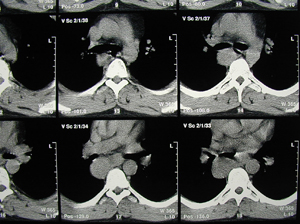

Εικόνα 2 α-γ

Αξονική τομογραφία του θώρακος σε διαφορετικά επίπεδα. Διακρίνεται η παρουσία όγκου στο οπίσθιο μεσοθωράκιο που πιθανά να αποτελεί όγκο του οισοφάγου.